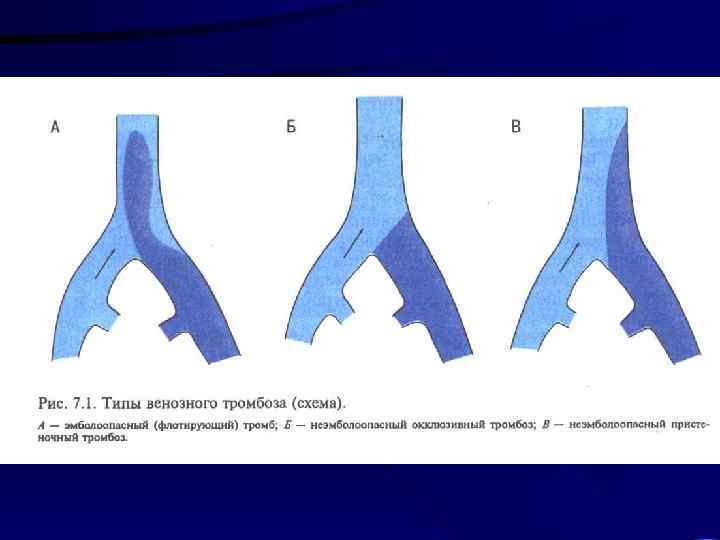

Лечение: 1. Консервативная терапия: a) Эластическое бинтование с возвышенным положением b) Гепарин c) Антибиотики d) Покой 5 -7 суток 2. При флотирующем или эмбологенном тромбозе хирургическое лечение: a) Установка Кава-Фильтра b) Пликация вен выше места тромба

Исходы: 1. При своевременном и адекватном лечении выздоровление 2. Развитие посттромбофлебитического синдрома 3. Тромбоэмболия легочной артерии с развитием инфарктной пневмонии или наступлением внезапной смерти

• Для возникновения тромбоза необходимо 3 фактора: 1. 2. 3. Повреждение сосудистой стенки при травме, воспалении, аллергии Изменение физико-химических свойств крови, обезвоживание, нарушение нервной регуляции жидкого состояния крови (свертывающей и противосвертывающей систем), воздействие токсинов Замедление тока крови